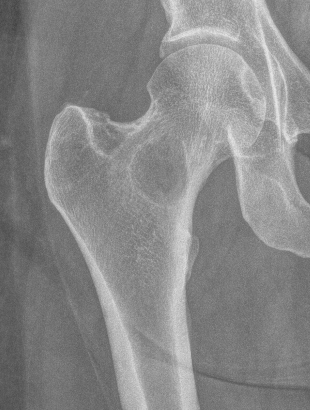

Mirels prediction system for pathological fracture

- quantify risk of pathological fracture

- weighted scoring system

- non fracture group mean score 7

- fracture group mean score 10

- score of 9 fracture risk 33%

Four risk factors

| 1 | 2 | 3 | |

| Site | Upper limb | Lower limb | Peritrochanter |

| Pain | Mild | Moderate | Mechanical |

| Lesion | Blastic | Mixed | Lytic |

| Size | < 1/3 | 1/3 - 2/3 | 2/3 |

Guidelines

Suggest surgical intervention score 9 or more

- 7 or less: radiotherapy

- 8: fracture risk is 15%